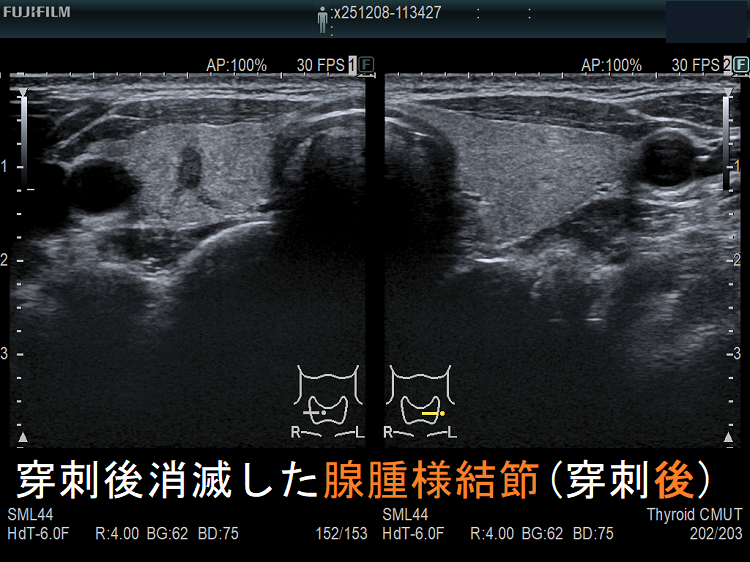

穿刺細胞診後内部融解

ケース①

ケース②

![穿刺後消滅した腺腫様結節(穿刺後) [拡大] 穿刺後消滅した腺腫様結節(穿刺後) [拡大]](../images/basic/basic5/images20251216212323.png)